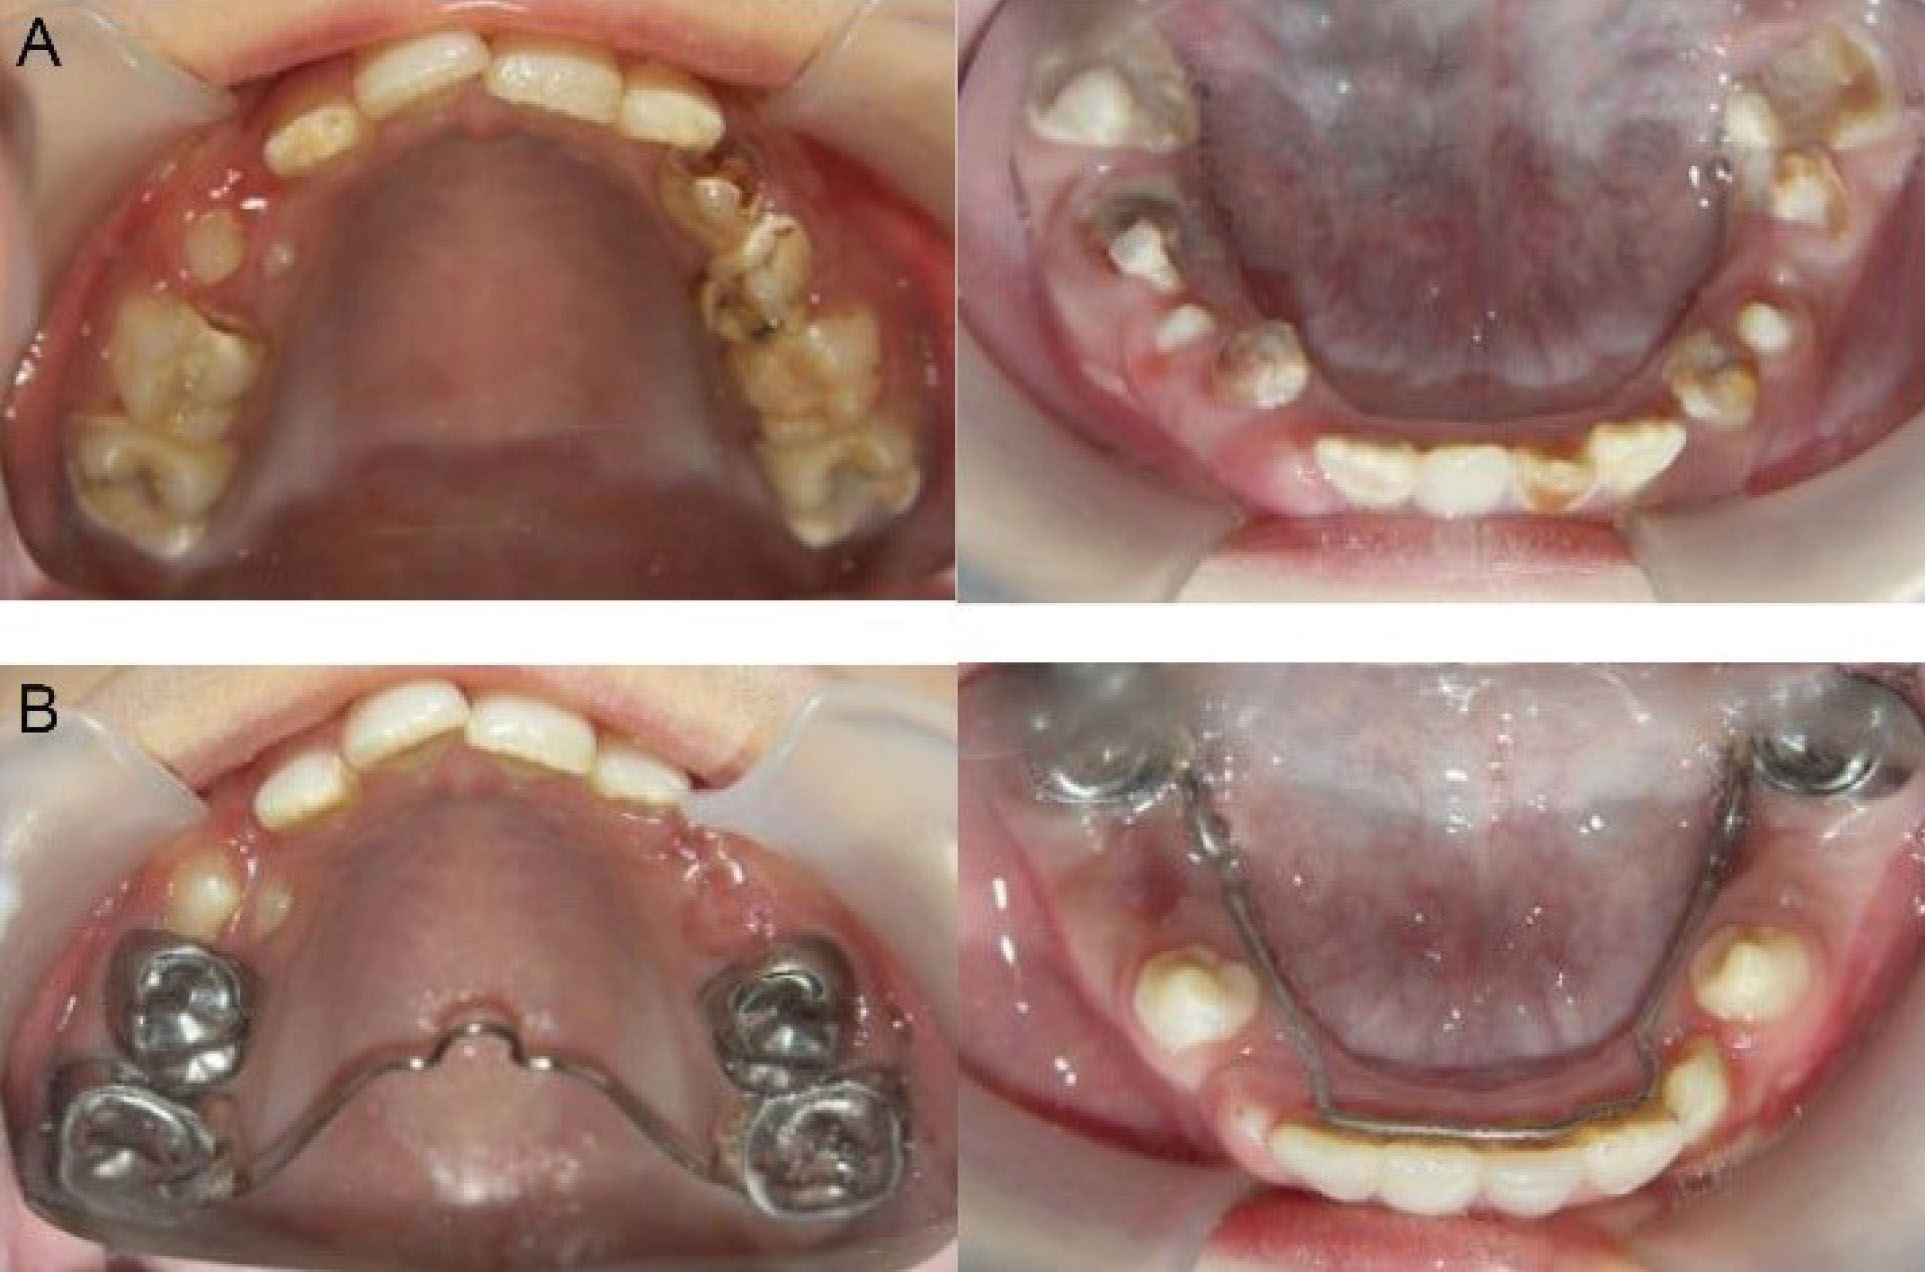

A cephalometric radiograph (Figure 5) analysis revealed a hyperdivergent clockwise rotation of jaw bases and confirmed skeletal open bite. To reduce the problem, trans-palatal arch (TPA) was considered for the patient to facilitate maxillary molar intrusion. Additionally, to control vertical dimension, a lingual arch was employed in the mandible (Figure 6). This conservative treatment approach was considered to simplify future comprehensive orthodontic treatments.

Figure 6.

(A) Occlusal View of Maxillary and Mandibular Arch Before Treatment and (B) Occlusal View of Maxillary and Mandibular Arch After Oral Rehabilitation, TPA of Maxillary Arch for Molar Intrusion and Lingual Arch of Mandibular Arch for Vertical Control. Note. TPA: Trans-palatal arch.